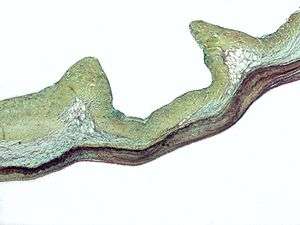

.webm.jpg)